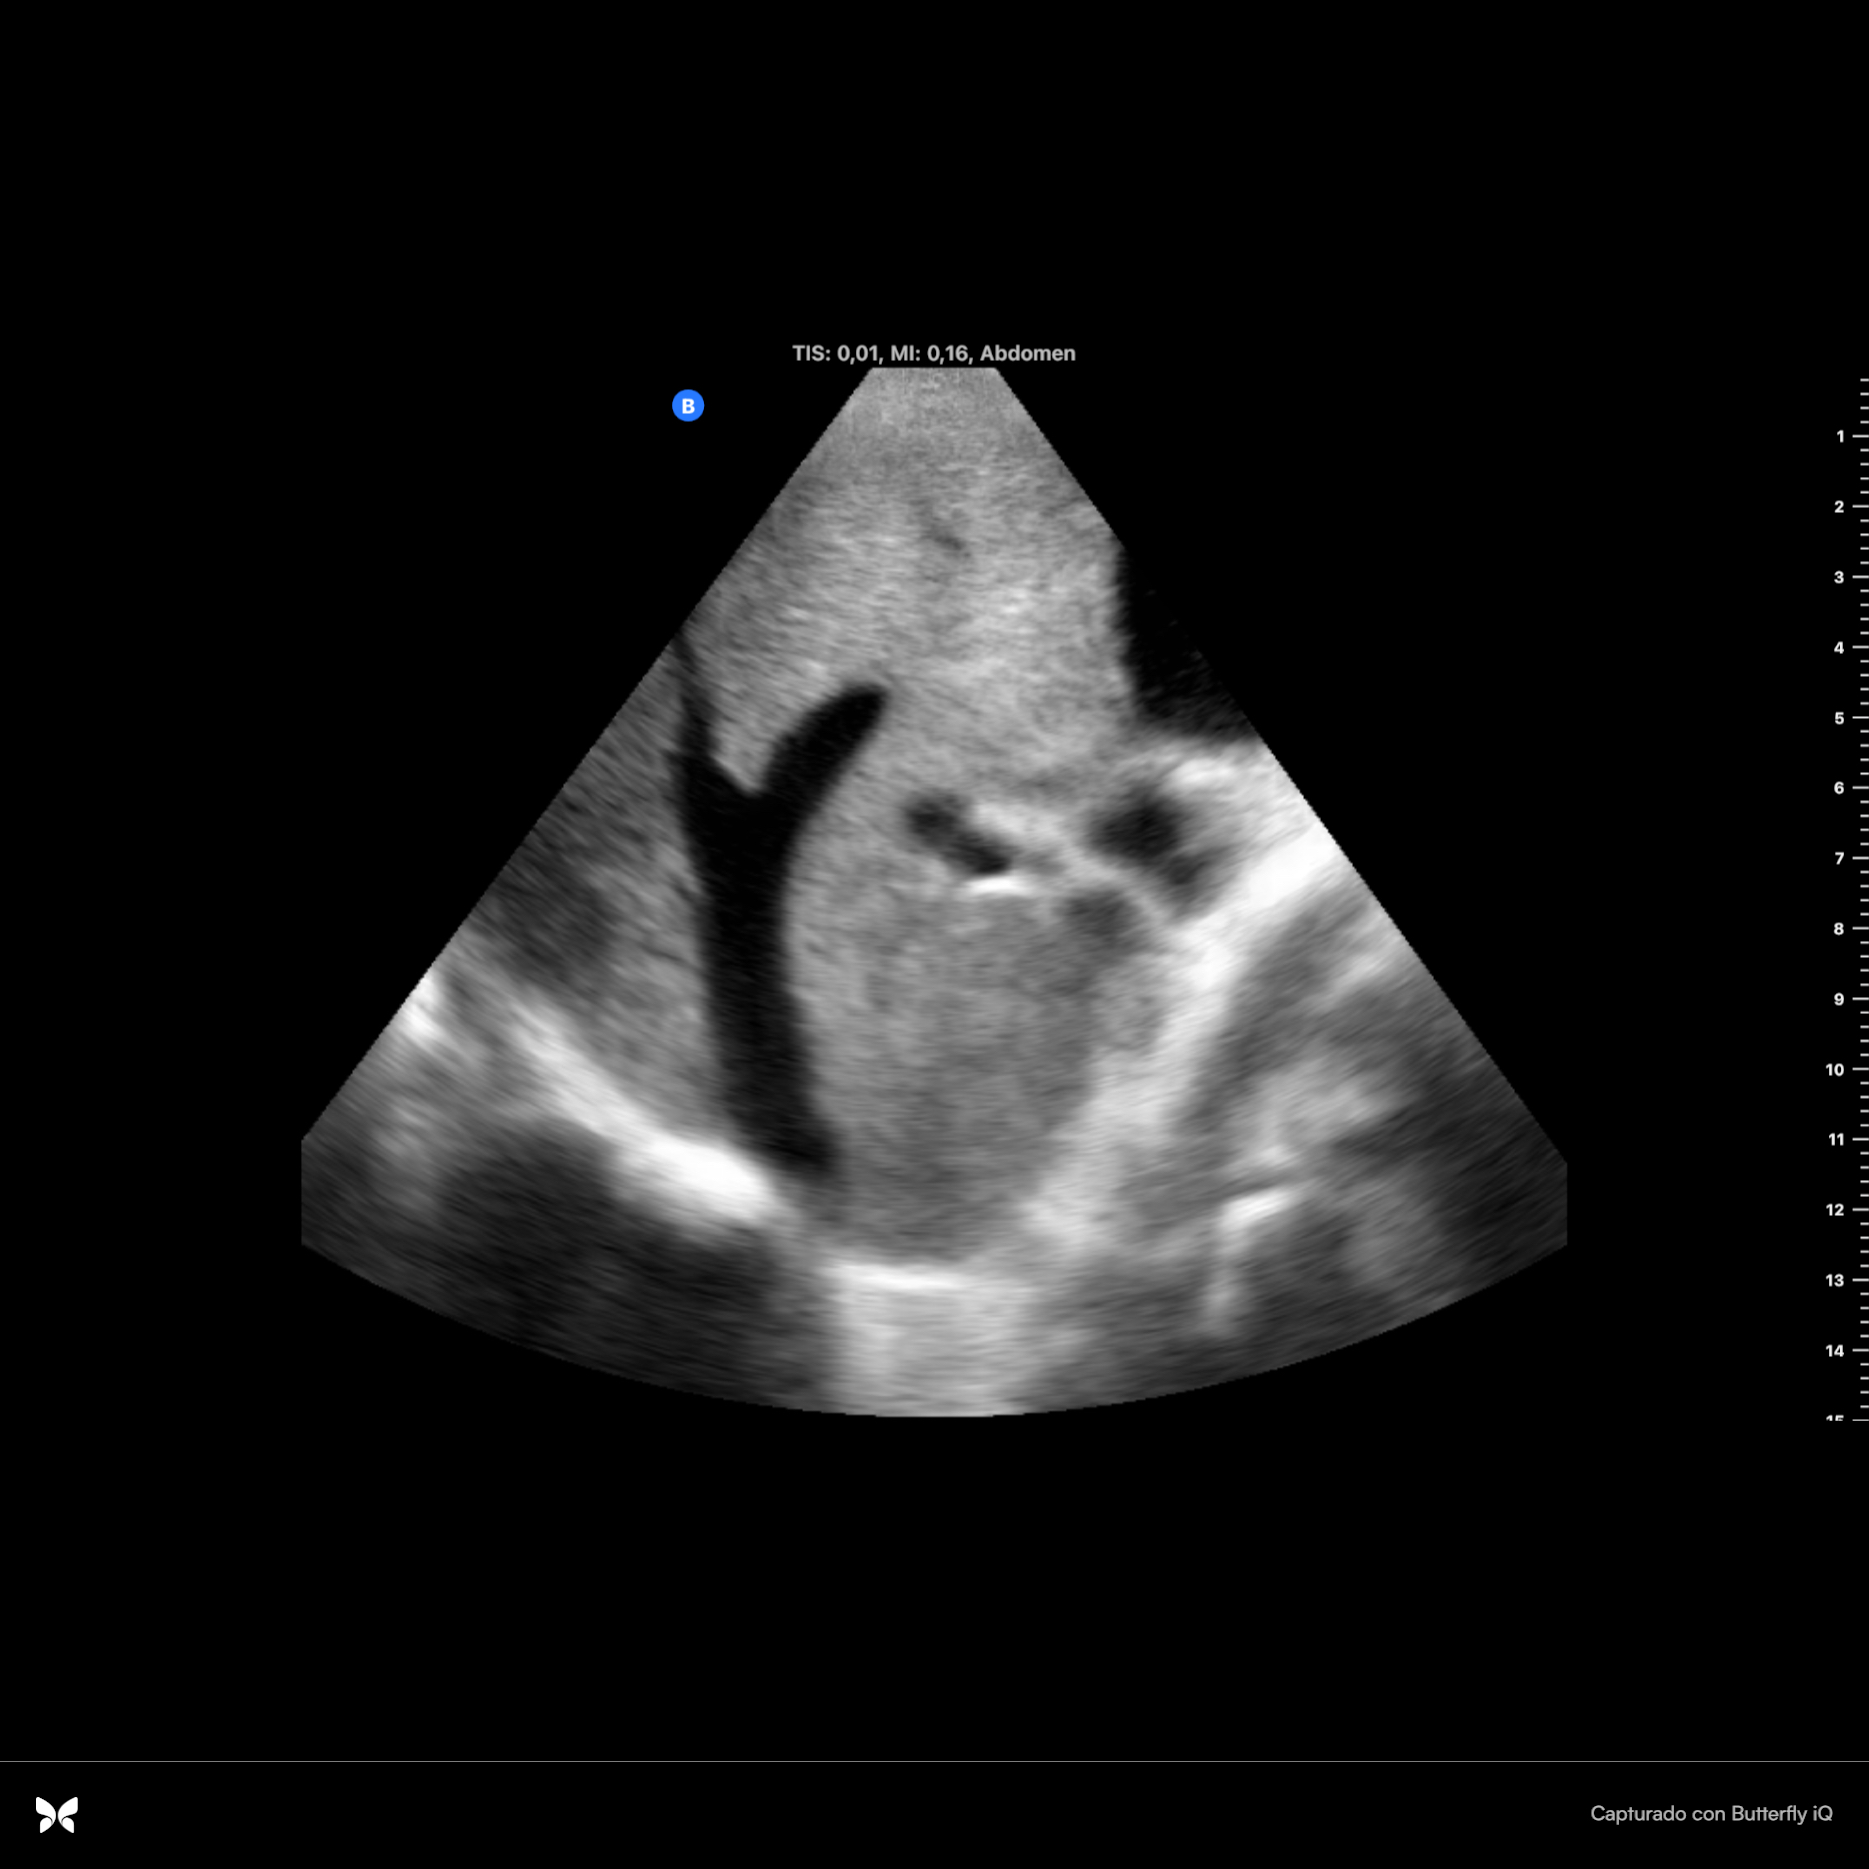

Se observan dos imágenes hiperecoicas en infundíbulo de vesícula que dejan sombra acústica posterior, una de ellas de 2 cm x 0.94 cm con aumento de grosor de vasos suprahepáticas. Parénquima hepático sin alteraciones. Se observa espacio anecoico superior al diafragma. Resto sin hallazgos.

En ecografía hospitalaria se observa claramente la dilatación de vía intra y extrahepática: colédoco con calibre de hasta 18 mm. Además se describen más hallazgos de insuficiencia cardíaca tales como líquido perivesicular y derrame plural derecho de espesor de hasta 7.5 cm y atelectasia del parénquima pulmonar.